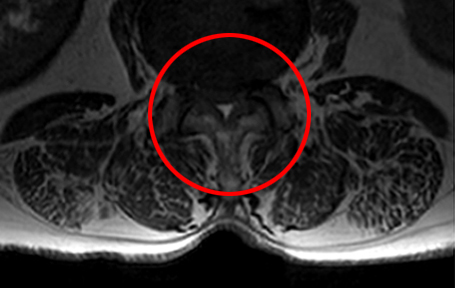

MRI로 본 중증 척추관협착증

• 모커리한방병원 MRI로 본 중증 척추관협착증 이미지

중증 척추관협착증 상태

(척추관의 공간이 거의 막혀 있는 상태로,

신경을 압박하여 정상적인 보행이 어려워짐)